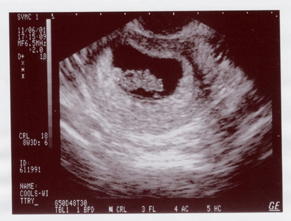

November 6th, first glimpse of our baby.

(11/6 first glimpse > 6/11 born !!!)